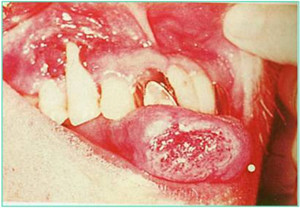

3癌性口腔溃疡

特点:多见40岁以上,男性多见;溃疡深浅不一,边缘不齐。底部菜花状周围及基底硬;好发于舌腹、舌缘、口角、软腭复合体。呈恶病质。